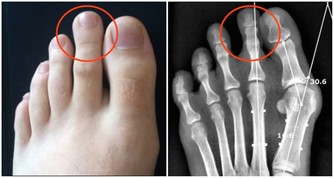

白天咳得少,經常在夜間兩三點時咳醒哭鬧,而且鼻子喘氣聲音特別大,睡眠中總是哼哼唧唧不安穩,可能是肝火旺盛,要想辦法降肝火。也有可能是上呼吸道阻塞,建議帶寶寶檢查耳鼻咽喉。

晚上不咳白天咳,有時唱歌、運動或大聲講話時咳嗽,可能是咽炎犯了,通常孩子的咽部是紅腫的,要及時消炎,給孩子多餵些水喝。

不僅咳嗽,還有胸悶、痰中帶血的情況,可能是心臟和肺部出現嚴重問題,常常因為咳嗽不能安穩入睡,家長要重視起來。

不僅咳還有點喘,有“吼”聲,暗示肺部問題有點嚴重,建議找醫生處理,不要亂吃止咳藥。

家長要留心孩子的心肺功能,若是發現孩子最近一段時間總是清嗓子,不喜歡外出運動,體力下降了,可能是肺功能降低了,建議進一步到醫院確診。